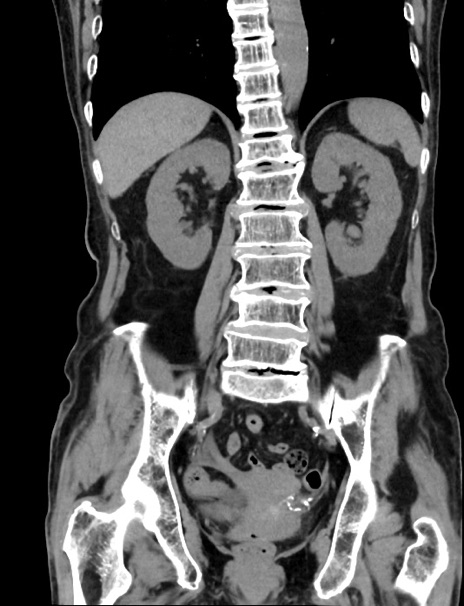

症例33(冠状断像)

【症例】70歳代 女性

【主訴】心窩部痛

【現病歴】延髄病変の精査・加療にて神経内科入院中。本日より心窩部痛あり。

【身体所見】右下腹部を中心に圧痛と反跳痛あり。

【データ】WBC 10900、CRP 0.02